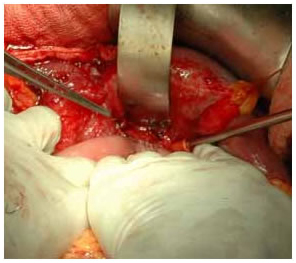

Intra Operative picture of Hepatico Jejunostomy